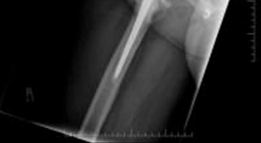

Discover the latest medical recommendations for Solving Severe Acetabular Bone Loss with Cup-Cage Reconstruction. Acetabular bone loss, often due to aseptic loosening of hip implants, manifests as acute groin pain and inability to weight bear. Radiological assessment typically reveals severe osteolysis of the ilium and ischium. Diagnosis centers on the extent of acetabular bone loss. Treatment, such as cup-cage reconstruction, aims to address significant defects and restore stability in complex revision total hip arthroplasty cases.

Severe acetabular bone loss represents one of the most formidable challenges in revision total hip arthroplasty. This complex clinical scenario is often encountered in cases of failed previous reconstructions, periprosthetic joint infection, extensive osteolysis, tumor resections, or significant trauma. The etiology is multifactorial, frequently stemming from aseptic loosening, septic loosening, component migration, or osteolysis secondary to polyethylene wear.

The classification of acetabular bone loss is critical for surgical planning. The Paprosky classification is widely adopted, categorizing defects based on the integrity of the host bone and the direction of component migration.

The American Academy of Orthopaedic Surgeons classification also delineates defects based on morphology, including cavitary, segmental, combined, protrusio, and pelvic discontinuity. Severe bone loss, particularly Paprosky Type 3A and 3B defects, frequently necessitates reconstruction techniques that go beyond conventional cementless hemispheric components with augments. Historically, structural allografts and isolated anti-protrusio cages were utilized; however, these demonstrated high long-term failure rates due to graft resorption and mechanical fatigue failure of the cages in the absence of biologic fixation.